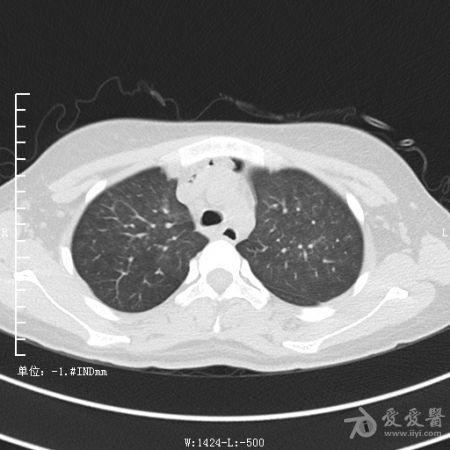

典型支气管扩张及肺水肿CT片

典型支气管扩张肺水肿